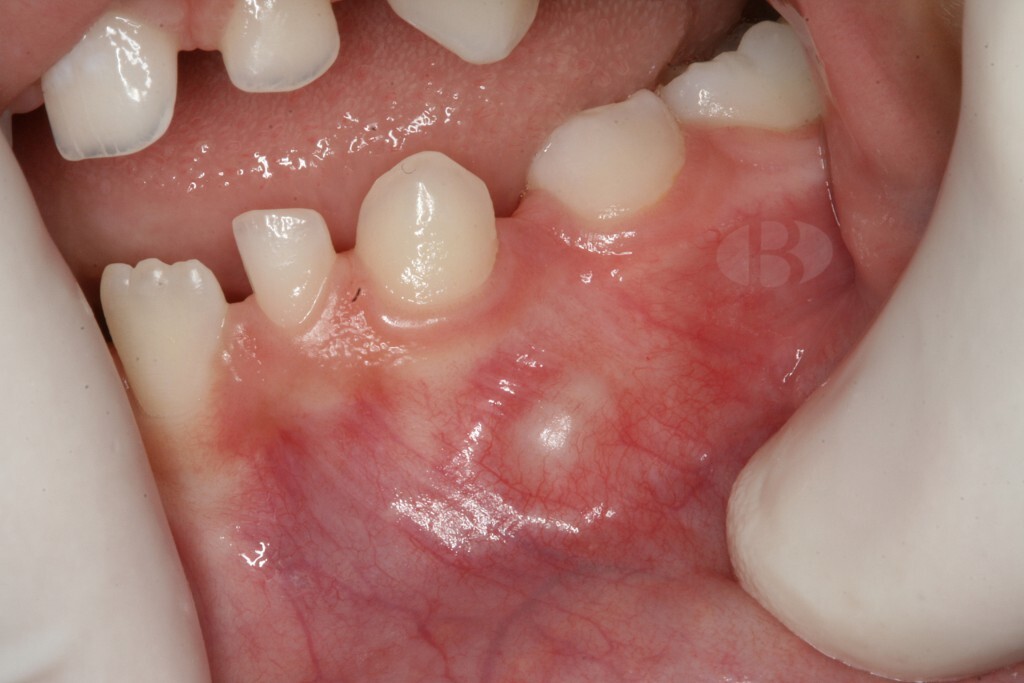

What Is An Odontoma And How Is It Treated

When you hear the word "tumor," there's a good chance you think of cancer. Fortunately, with an odontoma, that's not the case. While an odontoma is a tumor, it's a benign one and not uncommon. That alone is great news! However, odontomas usually require surgical removal. They're made up of dental tissue that resembles abnormal teeth or calcified mass that invade the jaw around your teeth and could affect how your teeth develop. Fortunately, treatment is pretty straightforward and the road to a tumor-free life is one frequently traveled.

Types of Odontomas

There are 2 main types of odontomas:

Compound:

Consisting of many, tiny tooth-like bits

Usually found in the lower jaw

Most often occurs during your teenage years

It affects men and women equally

Complex:

Made up of an assortment of dental tissue (enamel, dentin, etc.)

Usually found within the upper jaw

Most often occurs during your 20s

Diagnosis and Symptoms

Since odontomas grow internally around your teeth, an X-ray from your dentist is necessary to identify them, notes the AAPD. The shape will indicate to your dentist whether it's compound or complex. While they are asymptomatic, the West Indian Medical Journal Review notes your odontoma could cause:

Pain

Discomfort

Swelling

Tooth displacement

Nearly 80% of those affected by odontomas, though, have teeth that haven't erupted yet. Plus, since they're noncancerous, they rarely grow back after removal.

Removal

Removal surgery has been the tried-and-true treatment plan for odontomas — especially if they are causing any pain or affecting your teeth to erupt unnaturally. Some other things to know about odontoma removal surgery:

An oral or maxillofacial surgeon should consult your dentist on the surgery

The unerupted tooth associated with odontoma could be extracted if it's not developing correctly

If you have a tooth that needs extraction, discuss tooth replacement options and alignment issues with your dentist and/or orthodontist

Going through surgery is most likely your path should you be stricken with odontomas. But, it sure beats radiation or chemotherapy you'd have to face with cancer. Plus, the surgery to remove your odontomas is very common with few complications. Just remember to see your dentist regularly so they can identify the odontomas as early as possible on your X-rays.